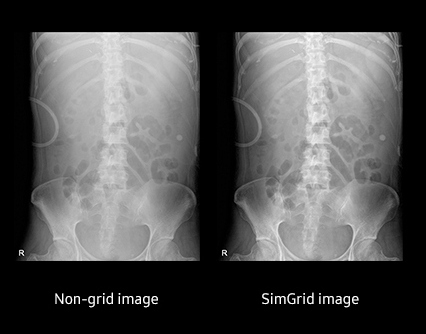

Функция виртуальной решетки SimGrid (Опционально)

Функция SimGrid уменьшает артефакты, связанные с неточным позиционированием, количество повторных снимков, а также обеспечивает высокое качество визуализации без использования решетки.